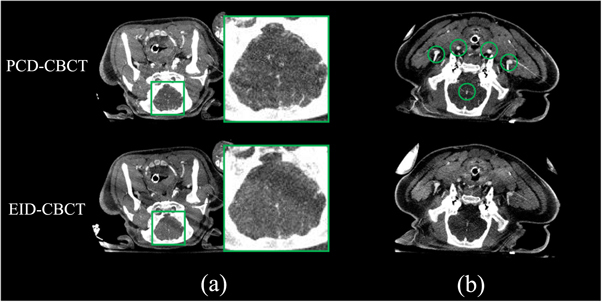

3.2. 3D imaging results

The UHR PCD-CBCT 3D reformatted images in figure 5 show improved delineation of the stent wires compared to the EID-CBCT images even when the PCD pixels are 2 × 2 binned to match the detector pixel size of the EID. Again, note that the unbinned (1 × 1) EID-CBCT was acquired under a longer 20 s rotation rather than a 7 s rotation due to detector readout speed limitations when the pixels are unbinned. These images are similar to those obtained with a more narrow PCD-CT in previous work (Treb et al 2022) but can be obtained with a single gantry rotation rather than with the multiple rotations needed to obtain sufficient z-coverage in the previous work. For the in vivo animal study, figure 6 shows PCD-CBCT and EID-CBCT MIPs of the brain region of two swine subjects covering the entire axial cross-section. Figure 6(a) shows several small cerebral vessels that are visible in the PCD-CBCT image but are missed by the EID-CBCT. This result is consistent with previous literature on the benefits of PCDs for CTA (Harvey et al 2019), and is due to the more optimal photon energy-weighting of the PCD as well as improved spatial resolution potential over the EID. The average CNR over the five larger vessels in figure 6(b) was measured to be 8.3 (range: (6.2, 10.3)) in the PCD-CT images and 4.2 (range: (3.3, 5.4)) in the EID-CBCT images, resulting in an average CNR improvement of 103% (range: (29%, 151%)).

Figure 6.

PCD-CBCT and EID-CBCT MIP images of an in vivo swine subject demonstrating (a) improved visualization of small peripheral vessels and (b) improved CNR in the five indicated vessels in the PCD-CT image. The pure EID images are displayed to compare to the PCD image rather than displaying a fused PCD-EID image. Image display range: [−100 to 300 HU].